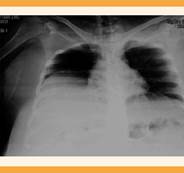

El estudio ecográfico abdominal y pélvico mostró dificultad técnica para su evaluación, por aumento del panículo adiposo. Aun así se logró evidenciar una tumoración heterogénea de origen uterino, de aproximadamente 30 cm de longitud y 20 cm de ancho, que ocupaba la totalidad de los cuadrantes abdominales superiores. Además, se corroboró el embarazo intrauterino, con feto vivo, movimientos y fetometría promedio de 23.3 semanas. El peso fetal estimado fue de 589 gramos. La placenta corporal, ubicada hacia el lado izquierdo, no afectaba la localización del leiomioma principal. El informe de los estudios de laboratorio al ingreso al hospital fueron: 21,400 leucocitos por mm3, hemoglobina 8.5 g/dL, hematocrito 28%, 324,000 plaquetas por mm3, tiempo de protrombina 12.7 segundos, tiempo de tromboplastina 29.6 segundos, relación internacional normalizada (INR) 1.2, fibrinógeno 1057 mg/dL. En la radiografía de tórax se apreció la reducción de los volúmenes pulmonares y elevación del diafragma. Figura 1

Figura 1 Radiografía de tórax en la que se evidencia el efecto de masa que provoca la tumoración con la consecuente afectación de la ventilación.